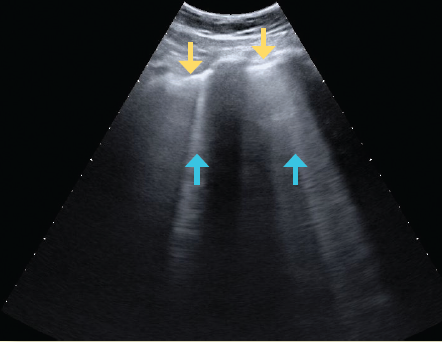

El ultrasonido es un método seguro, transportable a la cama del paciente, libre de radiación ionizante y de bajo costo, por lo que es útil en el diagnóstico y monitoreo de pacientes con infección por SARS-CoV-218. El hallazgo principal en ultrasonido es la enfermedad intersticial aguda, que produce artefactos hiperecoicos verticales que se apartan de la línea pleural, llamadas líneas B. El pulmón que pierde su contenido aéreo progresa de presentar un patrón pulmonar normal (con líneas A, las cuales se caracterizan por ser horizontales, cortas e hiperecoicas) a observar líneas B no coalescentes, después líneas B coalescentes hasta llegar a la consolidación19-21 (figuras 5a, 5b, 5c, 5d).

Figura 5c Ultrasonido en escala de grises del tórax, donde se observa la línea pleural (flechas amarillas) y las líneas B coalescentes (flechas azules) que traducen mayor engrosamiento intersticial